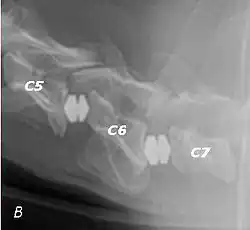

Doberman C6-C7 and C5-C6 traction responsive myelopathy A

Doberman C6-C7 and C5-C6 traction responsive myelopathy B

T2 weighted MRI in neutral (A) and linear traction (B) of a seven-year-old Doberman with a two-year history of cervical pain treated with NSAIDs and presented acutely tetraplegic: A C6-C7 and C5-C6 traction responsive myelopathy are evident on MRI. The spinal-cord hyperintensity seen at the C5-C6 is suggestive of chronic lesion and most likely responsible for the chronic history of cervical pain, while the C5-C6 lesion was most likely responsible for the acute tetraplegia.